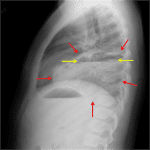

Age: 5

Sex: Female

Indication: Fever, shortness of breath

Sample ReportLeft lower lobe rounded opacification with an air-fluid level, which is concerning for a lung abscess.

Small left pleural effusion.

Additional segmental right perihilar airspace opacities likely represent atelectasis.